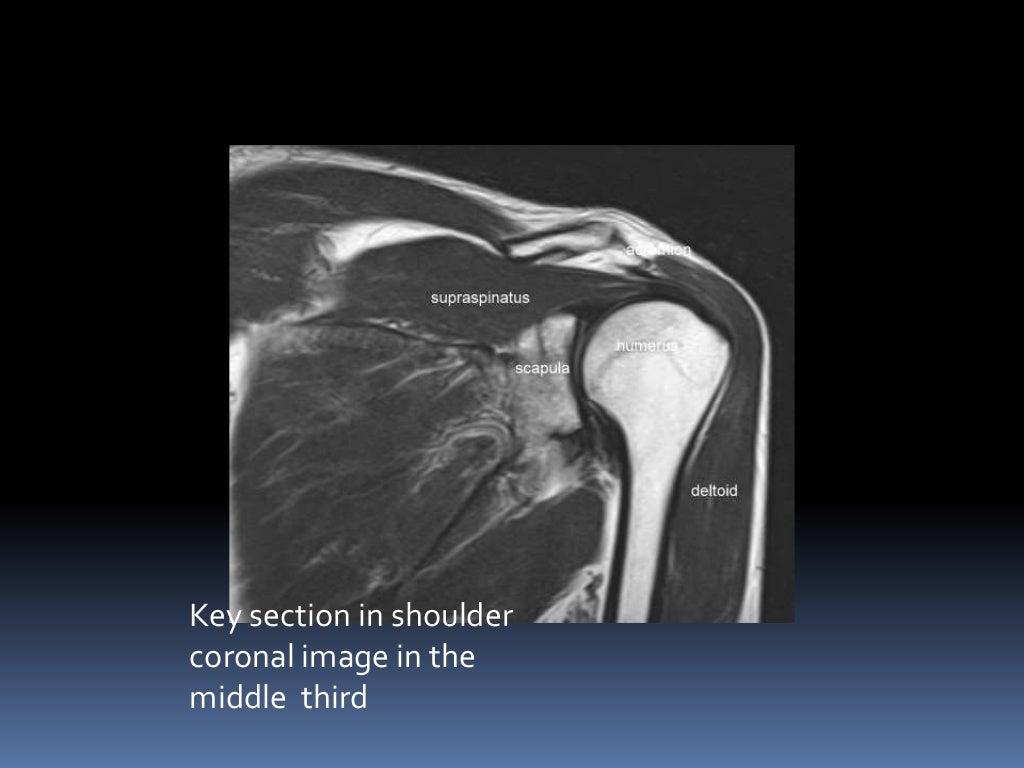

MRI OF SHOULDER INJURY Shoulder Mri Images Injuries this paper will review mri techniques for evaluating the shoulder, normal shoulder anatomy and mri. learn how to create a radiological report of an mri shoulder with coverage of the most common anatomical sites of possible pathology. a shoulder mri is a scan that shows soft tissue problems in your shoulder, such as rotator cuff injury or. Shoulder Mri Images Injuries.